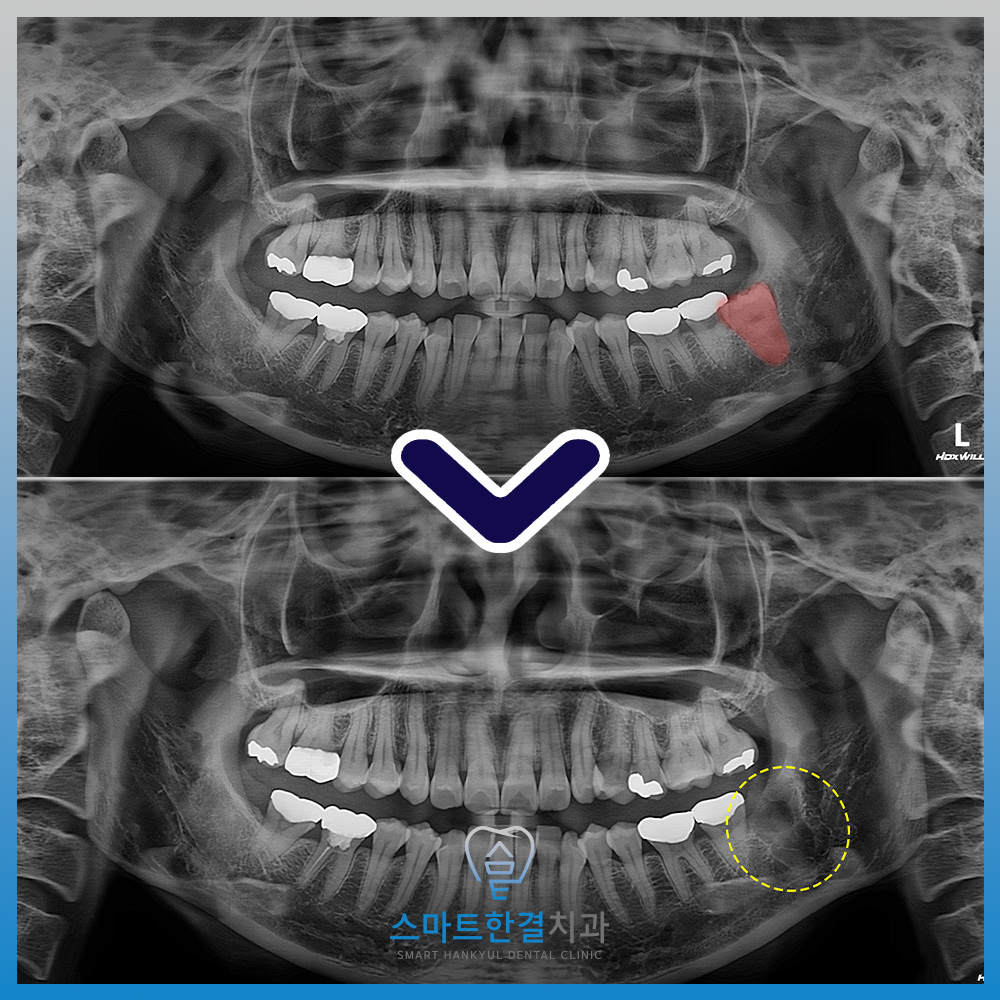

깨끗하게 발치가 된 모습 이에요!

수술적인 방법으로

잇몸을 절개하고

뼈를 다듬고 치아를 분할하며

발치를 진행했어요.

이 과정에서 중요한 점은

발치 시 앞 치아에 미치는 영향을

줄이는 것이었어요.

환자분의 앞 치아는 현재

크라운이 씌워져 있는 상태였기 때문에,

발치 과정에서 과도한 힘이 가해지면

크라운이 탈락할 위험이 있었어요.

이를 방지하기 위해,

발치 시 힘을 조절하며

섬세하게 작업을 진행했답니다. (^^)

화서동치과 스마트한결의

치료 전후 사진이에요.

환자분께서는 수술적으로 발치를 진행하였지만

금방 발치하여 시간이 오래 걸리지도 않고,

불편함 없이 마무리할 수 있어

매우 만족해 주셨어요.